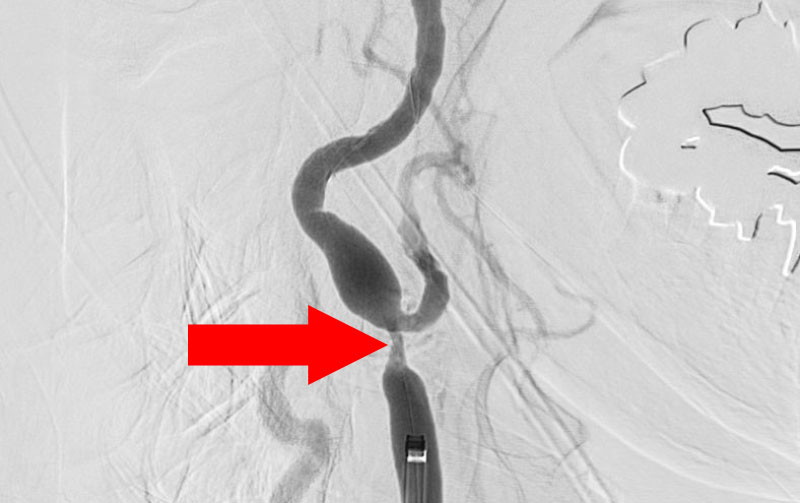

症例 '22年10月

No.

1289

'22年10月17日

右頚部内頚動脈狭窄症

80代

院内外来

手術写真

治療

前

中

後

手術日